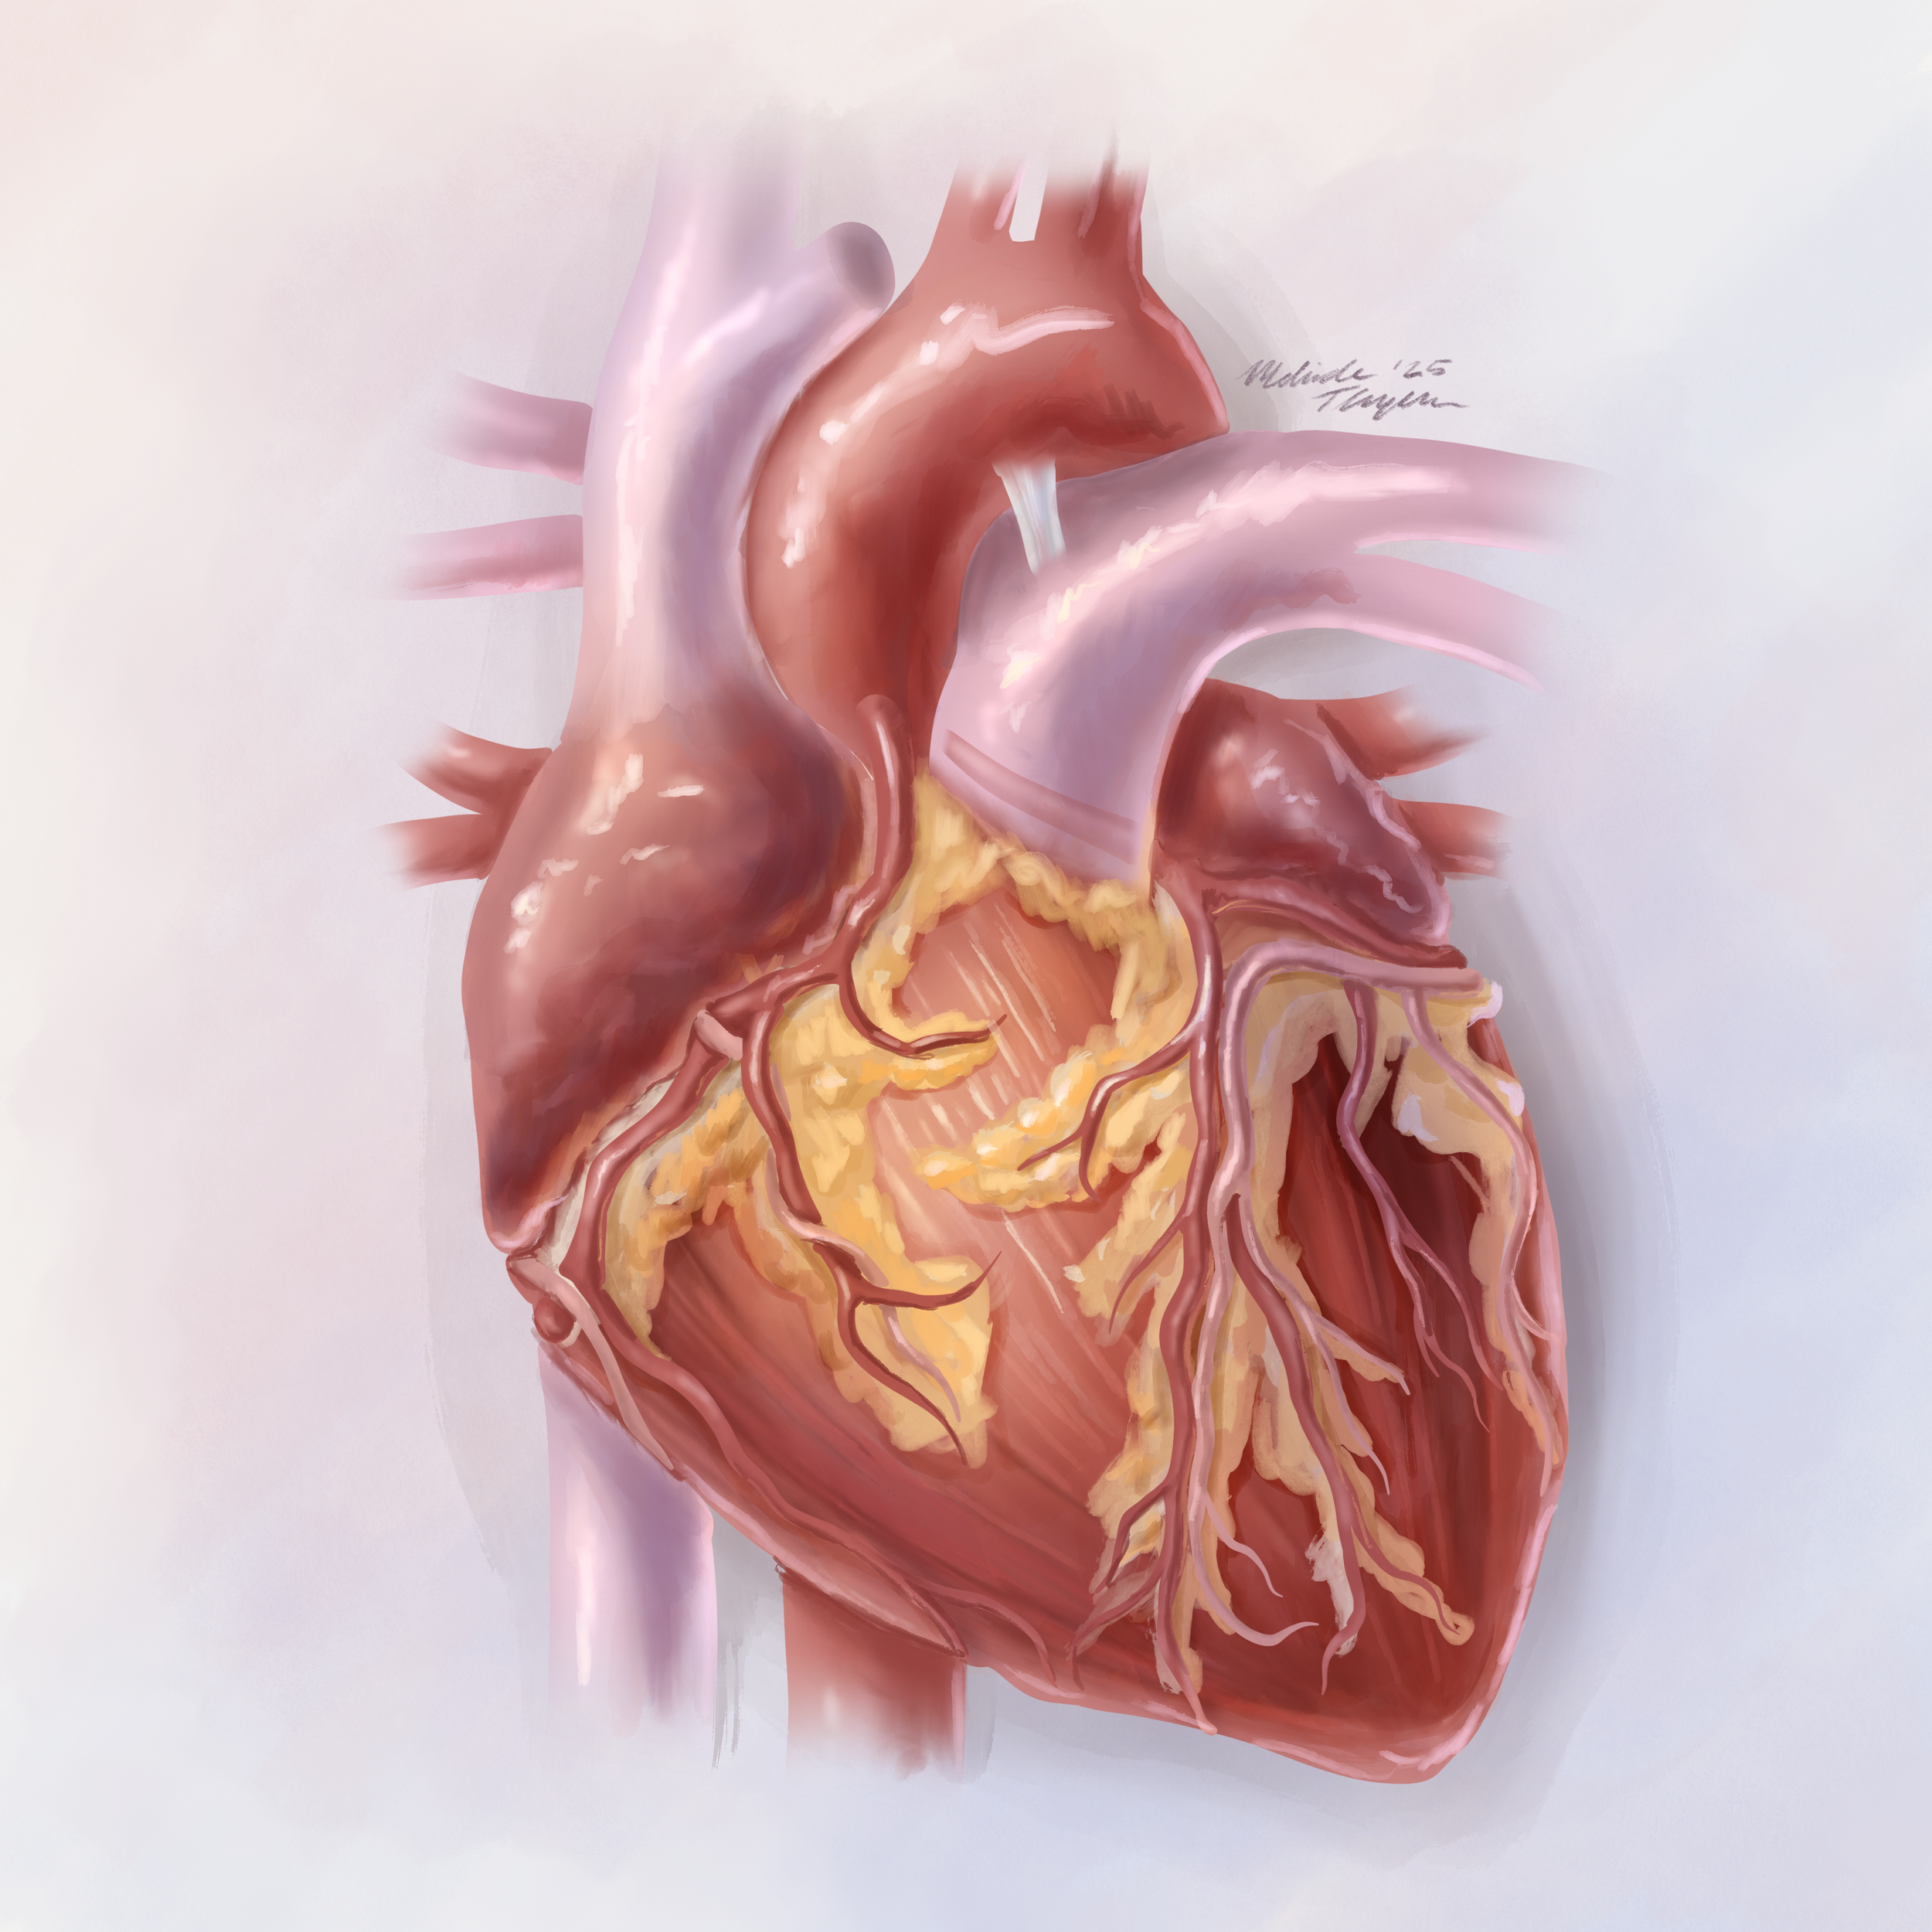

Organ study: The human heart in a painterly style